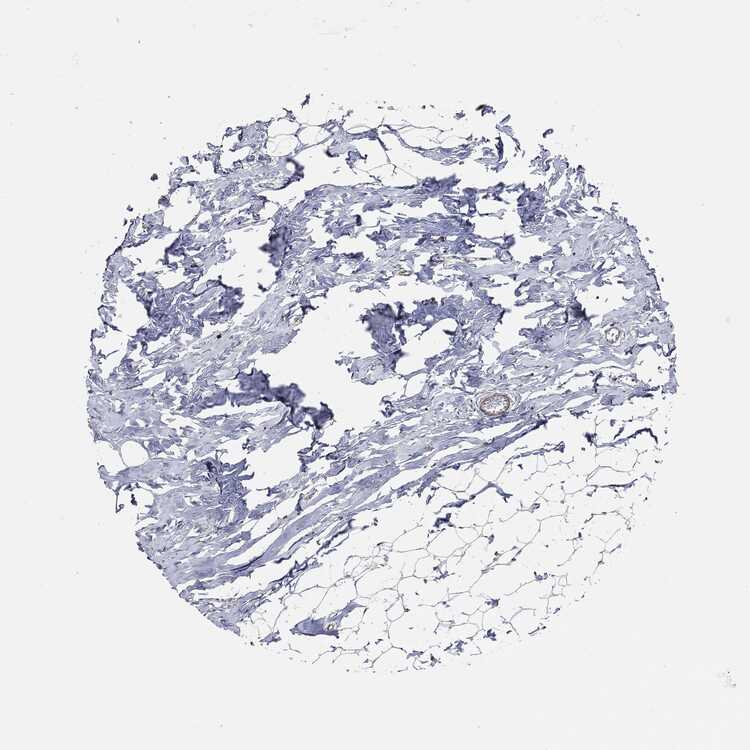

TISSUE PRIMARY DATA BREAST Show tissue menu

BREAST - Antibody stainingi

Antibody staining in the annotated cell types in the current human tissue is reported as not detected, low, medium, or high, based on conventional immunohistochemistry profiling in selected tissues. This score is based on the combination of the staining intensity and fraction of stained cells.

Each image is clickable and will lead to virtual microscopy that enables deeper exploration of all samples and also displays staining intensity scores, fraction scores and subcellular localization as well as patient and tissue information for each sample.

Antibody HPA073281Antibody CAB025316

Adipocytes Not detectedMedium

Glandular cells HighMedium

Myoepithelial cells Not detectedMedium